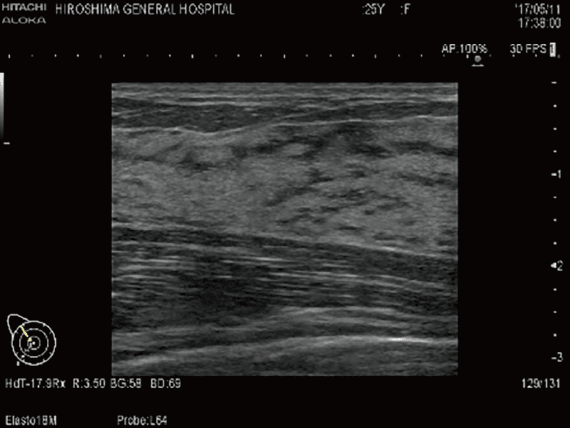

乳房超音波検査

乳房に超音波を照射し,乳腺を観察する検査です。乳腺内の腫瘍の有無や大きさ,リンパ節への転移の有無などの評価に用いられます。